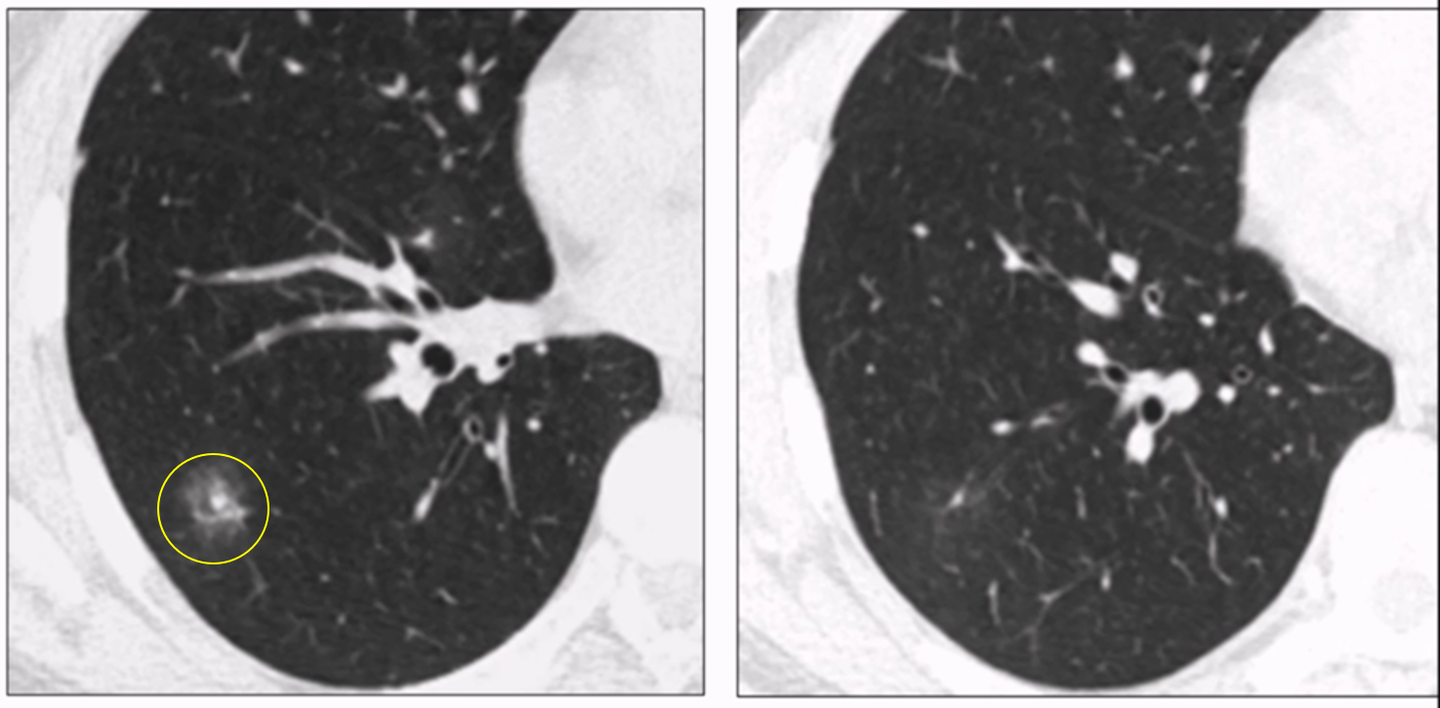

随着肺癌CT筛查的广泛推广,人们对于肺部磨玻璃结节(GGN)的关注也日益增加。GGN是指在肺部CT扫描中出现的一种密度增高的影像,通常不足以遮盖血管和支气管的轮廓,其边界可能清晰也可能模糊。但是,对于这种结节,我们应该如何应对呢?

首先,让我们了解一下磨玻璃结节的特点。根据影像表现,可以将其分为纯GGN部分实性GGN。纯GGN指的是结节内部没有实性成分,而部分实性GGN则可能包含一些实性成分。对于患者而言,很多时候这些结节是在做其他检查或者是进行肺癌CT筛查时意外发现的。